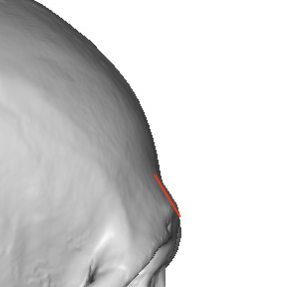

Key Surgical Principle

If it is the thin front wall of the sinus, shaving would enter the sinus, so the bone must instead be cut, repositioned, and fixed back.

- CT imaging is often obtained preoperatively to assess sinus size and the thickness of the obverlying bone of the nedial brow prominences. The lateral or tail of the brow is always solid bone.